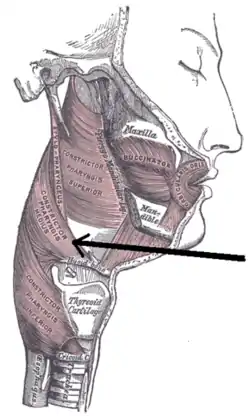

Hyoid bone. Anterior surface. Enlarged. Muscles of the neck. Lateral view.

Muscles of the neck. Lateral view. Middle pharyngeal constrictor muscle